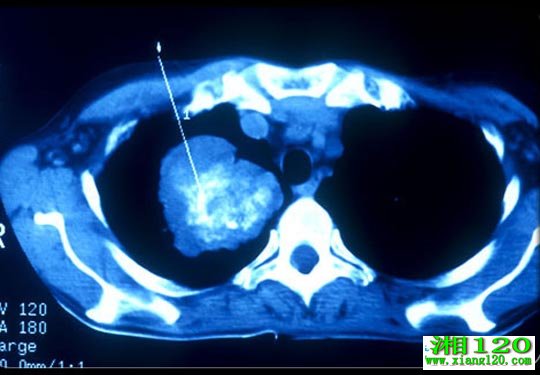

(2)CT检查:胸部CT是肺癌的最常用和最重要的检查方法,用于肺癌的诊断与鉴别诊断、分期及治疗后随诊。有条件的医院在肺癌病人行胸部CT扫描时范围应包括肾上腺。应尽量采用增强扫描,尤其是肺中心型病变的患者。CT是显示脑转移瘤的基本检查方法,有临床症状者或进展期病人应行脑CT扫描,并尽可能采用增强扫描。